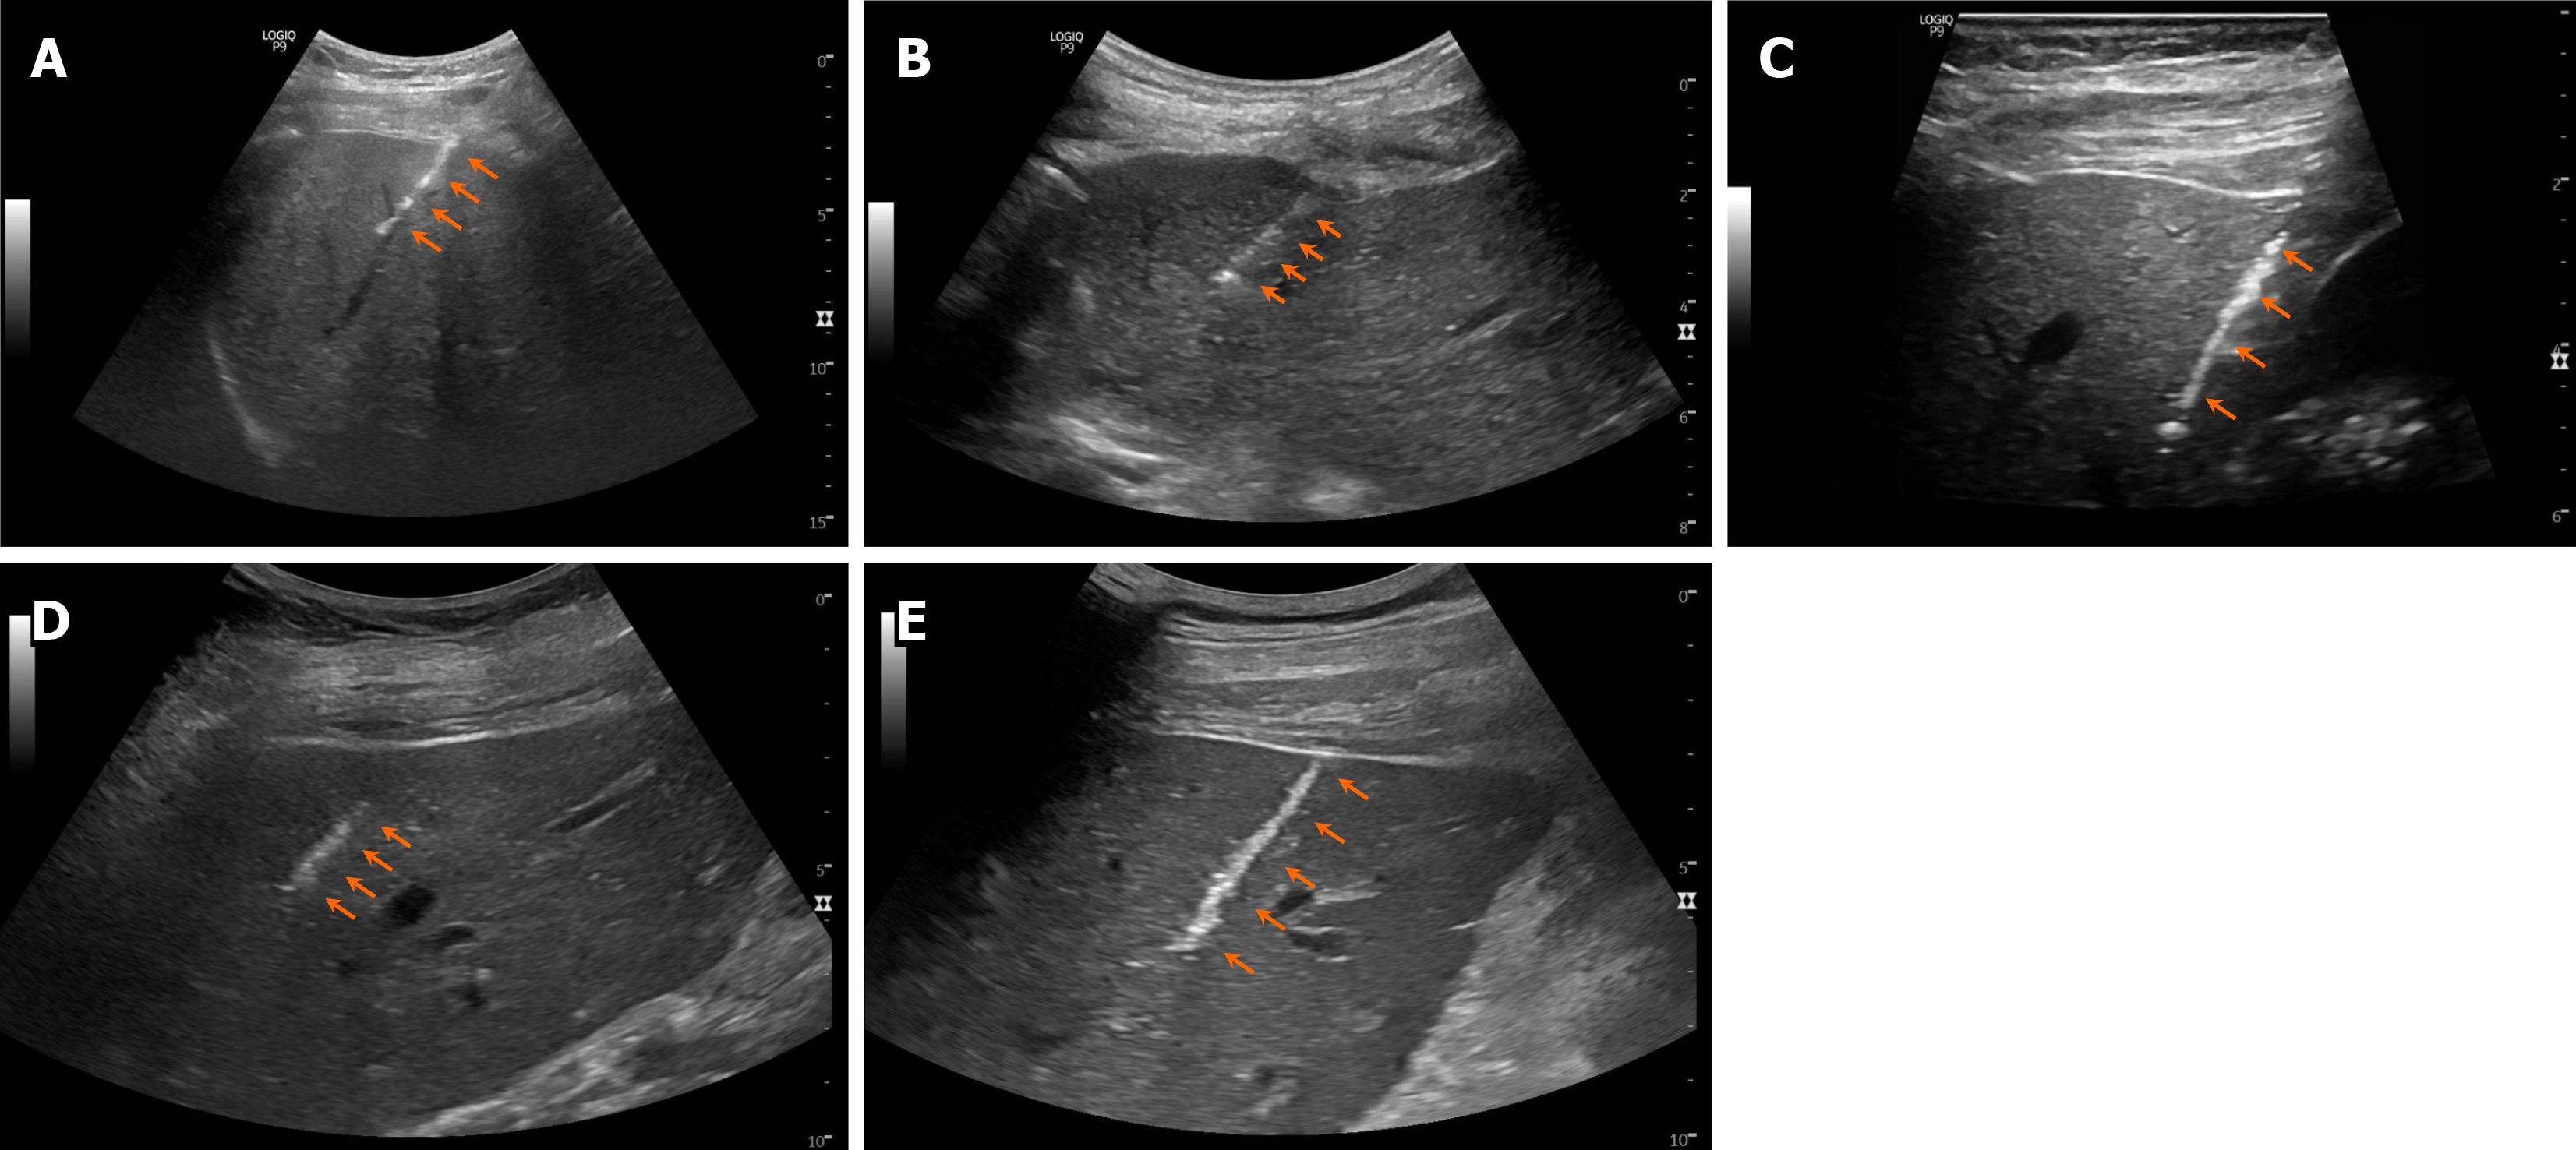

Figure 2 Post-procedure ultrasound images.

A-E: Post-biopsy ultrasound imaging demonstrates clearly defined echogenic, linear cautery tract (orange arrows) for case 1 (A), case 2 (B), case 3 (C), case 4 (D), and case 5 (E).